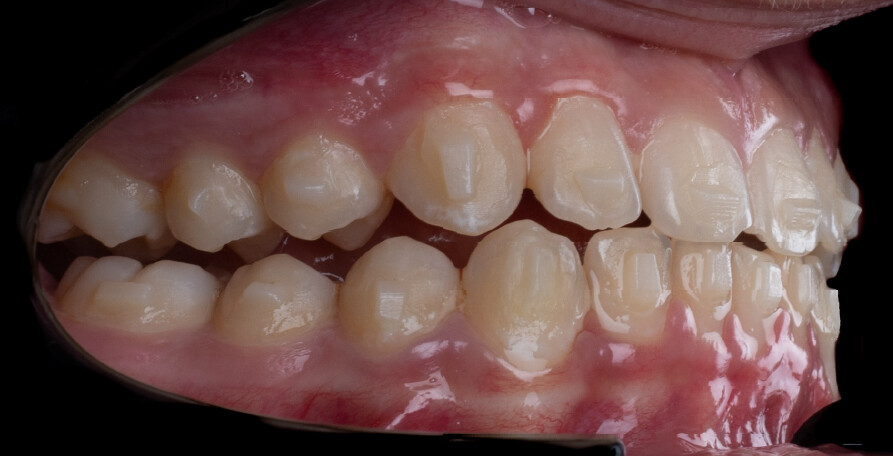

Um paciente do sexo masculino, com 13 anos de idade, apresentou-se com uma mordida profunda, caracterizada pela cobertura quase completa dos incisivos mandibulares. A avaliação clínica revelou apinhamento em ambas as arcadas, rotações dentárias e proclinação dos incisivos laterais superiores, contribuindo para as preocupações estéticas do paciente. O perfil facial era retrusivo, consistente com retrognatismo mandibular, e não foram detectadas anomalias periodontais significativas.

O paciente apresentava uma relação esquelética de Classe II com molares e caninos bilaterais em Classe II e um padrão dentário de Classe II divisão 2. A mordida profunda estava associada a um apinhamento anteroinferior e a uma curva de Spee acentuada. A análise facial revelou boa simetria, um terço facial inferior ligeiramente aumentado e um perfil convexo caracterizado por retrusão mandibular e do mento. A competência labial estava ligeiramente reduzida, com diminuição do ângulo nasolabial e leve tensão do músculo mentoniano, fatores que comprometiam a harmonia facial global.